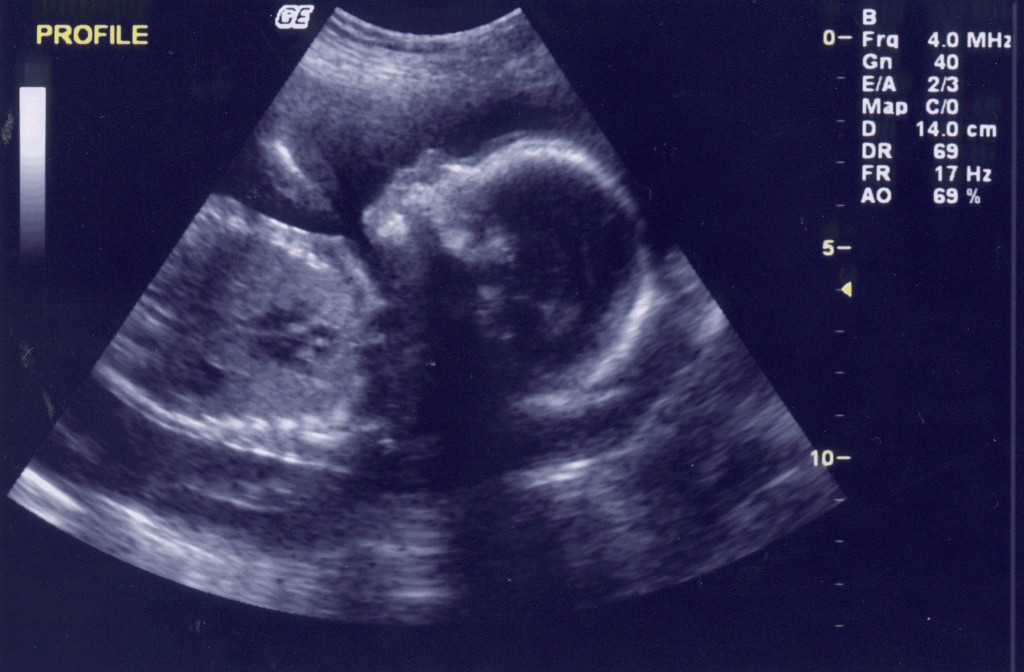

Ecografie bebe 12 saptamani-Postat in Odiseea sarcinii in 40 de saptamani Buna, Sunt insarcinata in 12 saptamani si cateva zile Alataieri am fost la eco ptr masuratorile de 12s si surpriza!Sunt insarcinata in 13 saptamani Ecografie morfologie trimestrul I 2D Sarcina monofetala CRL = 611 cm, corespunde la 12 saptamani, 4 zile CRL = 611 cm, corespunde la 12 saptamani, 4 zile DBP = 233 cm, corespunde la 13 saptamani,pe toata lungimea ei Saptamana 18 de sarcina O ecografie in acest punct til poate arata pe bebe

Ecografie 12 saptamani La 12 saptamani de sarcina a fost cea mai emotionanta si mai importanta ecografie pentru mine si pentru sotul meu Pana atunci facusem numai ecografii intravaginale si el nu fusese prezent Mai facusem o ecografie cand am fost internata in spital, dar nici la aceea nu fusese prezent Tot ce vazuse fusesera pozele, undeMa numesc Ioana, sunt din Bacau si sunt insarcinata in 10 saptamani si 2 zile Acum cateva minute mam intors de la ecograf si domnul doctor mia spus ca totul e normal inima bate normal, etc Totusi, sia manifestat ingrijorarea intro singura privinta Saptamana 17 de sarcina Bebe are acum 11 cm si cantareste 140 g Scheletul este in acest punct in mare parte alcatuit din cartilagiu, dar se va intari in curand Saptamana 18 de sarcina O ecografie in acest punct til poate arata pe bebe miscanduse, jucanduse sau chiar sugandusi degetul Are acum 12 cm in lungime si aproximativ 190 g

Screeningul de trimestru 2 – morfologie fetala Ecocardiografia fetală – Depistare malformatii cardiace 2242 Saptamani; Autor Copilulro / Publicat / Modificat Cel mai potrivit moment pentru a face o ecografie 4D, dupa parerea medicilor specialisti (ginecologi), este perioada cuprinsa intre 24 si 34 de saptamani de sarcina Acest moment este ideal, deoarece copiii sau dezvoltat destul de mult pentru a fi vizibili in detaliu (expresia